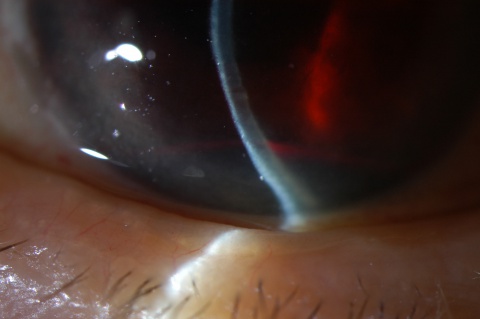

Diagnosis is made with slit-lamp examination of the anterior chamber. A large hyphema can be noted with pen-light examination alone.

The examination for a hyphema should consist of a routine ophthalmic workup (ie, visual acuity, pupillary examination, IOP, slit-lamp examination) as well as gonioscopy to evaluate the condition of the angle and trabecular meshwork. This is important especially in the setting of ocular trauma to gain an understanding of the extent of the trauma. This can be delayed until after the critical 5-day, high-risk, rebleed period, particularly when doing dynamic gonioscopy. Angle abnormalities such as peripheral anterior synechiae (PAS) and angle recession may commonly be found.[4] It is also critical to measure the height of the hyphema from the inferior limbus.

Signs

A large hyphema can be noted with pen-light examination alone. The height and color of the hyphema should be documented. Height can be measured in millimeters from the inferior corneal limbus. Color can vary from red to black depending on the time frame of the hyphema. Blood that has clotted will appear darker in appearance (black). It is important to evaluate intraocular pressure.